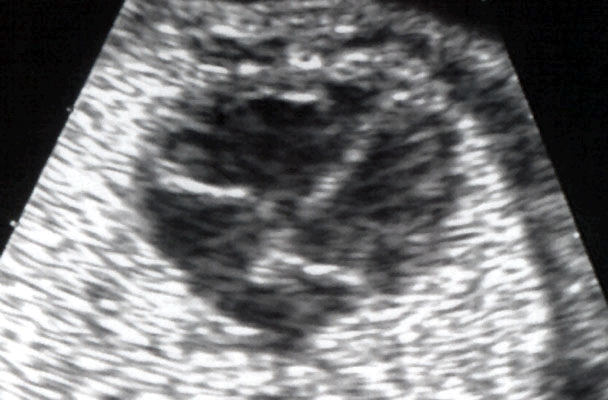

Coupe des quatre cavités cardiaques montrant la différence entre l'insertion

de la valve tricuspide et la valve mitrale sur le septum inter-ventriculaire